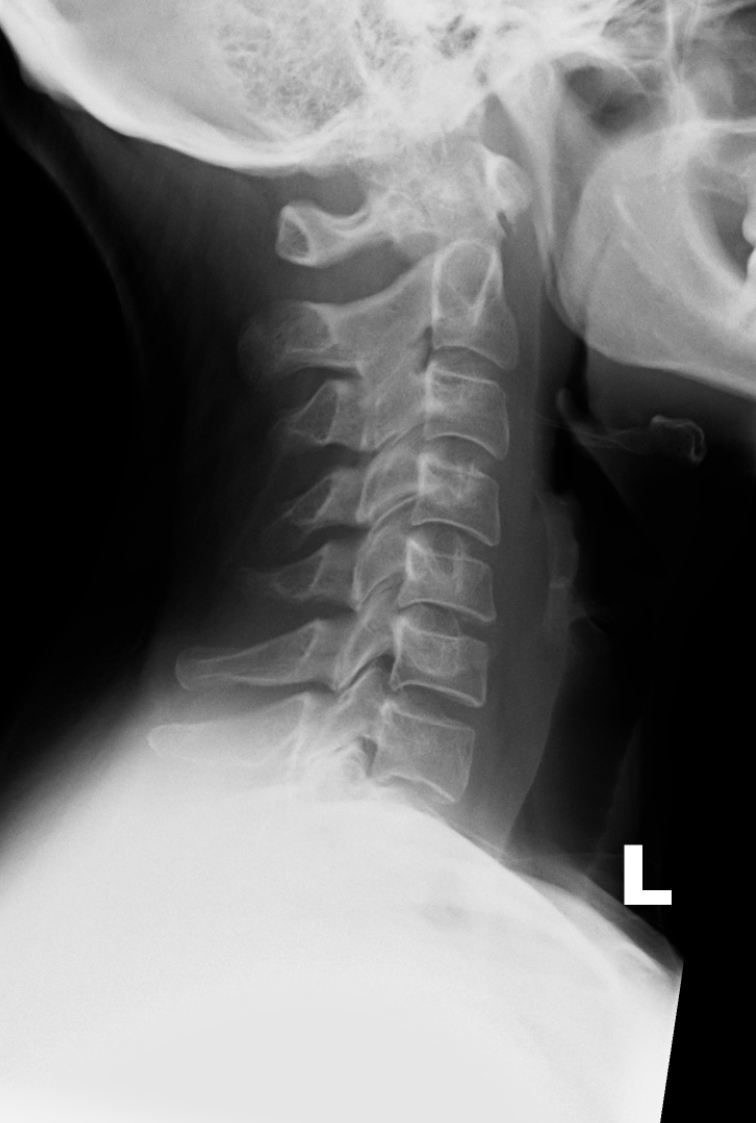

Female. Age 25. Road Traffic Accident (RTA).

Painful neck. Tenderness in the mid cervicle spine. No abnormal neurological findings.

Any evidence of a fracture and/or a subluxation?

RADIOGRAPHS